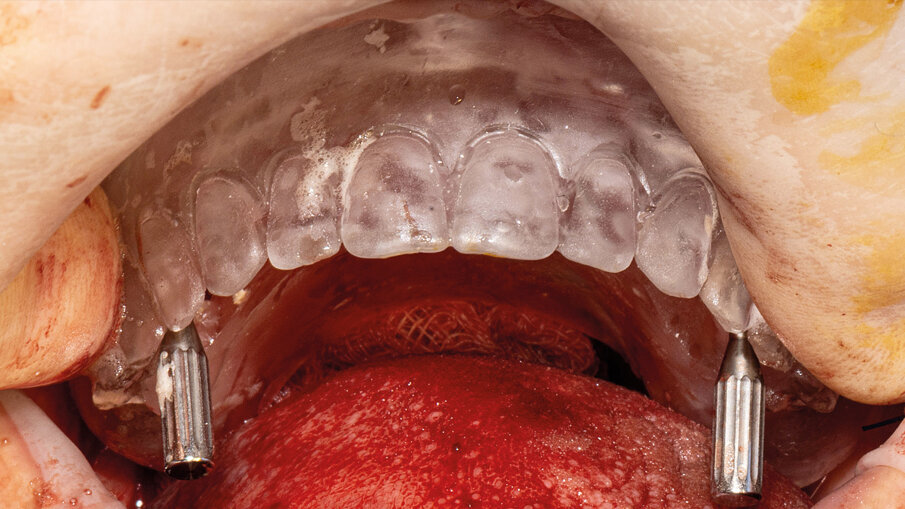

È presentata una riabilitazione con 4 impianti zigomatici (QUAD) in paziente con grave atrofia del mascellare. In questo caso la protesi con carico funzionale è stata consegnata alla paziente dopo 72 ore. Nelle immagini 1-4 viene mostrata la stereolitografia e la TC della paziente, mentre nelle immagini 5-7 viene mostrata la situazione iniziale e finale della paziente.

- inserimento dei monconi protesici nei 4 impianti collocati – 2 standard e 2 zigomatici – e controllo della loro congruità mediante mascherina chirurgica (Figg. 10, 11).